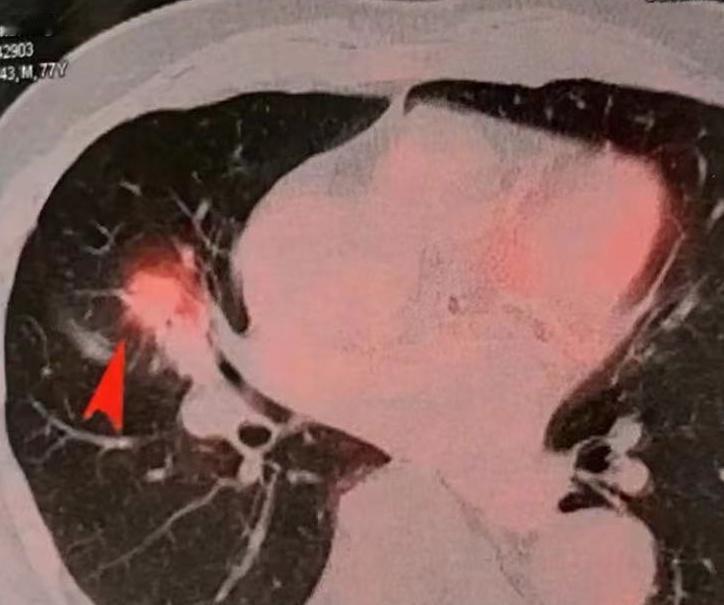

PET-CT做一次要花近万块,为什么这么贵?普通人有没有必要做?今天我们就来聊聊它的3大主要用途。 1、帮助判断肿瘤是良性还是恶性 比如肺里发现一个阴影,医生需要确定它的性质,这时候PET-CT就能派上用场。如果这个病灶代谢活性很低,或者基本不代谢,那良性可能性就比较大。 不过要注意,很多肺结节其实通过普通CT的形态特征,经验丰富的医生就能大致判断性质,不一定非要做PET-CT。尤其是磨玻璃结节,PET-CT的诊断准确率其实并不高。 2、用于精确的癌症分期 如果已经确诊肺癌,医生需要知道肿瘤有没有扩散到全身或者淋巴结,这时候PET-CT就很有用。它可以一次扫描全身,看其他部位有没有异常代谢,从而确定分期,指导后续治疗。 3、评估治疗效果 有时候,患者做完化疗、靶向或免疫治疗后,普通CT显示肿瘤大小没变化,按照传统看法,可能会认为药物没效果。 但PET-CT能看到更深层的信息,如果肿瘤代谢明显降低,即使大小没变,也说明药物起效了,肿瘤活性被抑制了。 那么问题来了:健康人做体检,有必要选择PET-CT吗? 其实对大多数人来说,真没必要!统计显示,90%以上的健康人做PET-CT检查,结果都是正常的。也就是说,你花了一大笔钱,很可能什么异常都查不出来。 更何况,PET-CT是功能成像和结构成像的结合,辐射剂量比普通CT要高不少。所以对健康人来说,花钱多、辐射大、检出问题的概率又低,怎么看都不划算。 常规体检,更推荐选择低剂量螺旋CT这类项目,辐射小,也足够满足基本筛查需求了。[玫瑰][作揖]